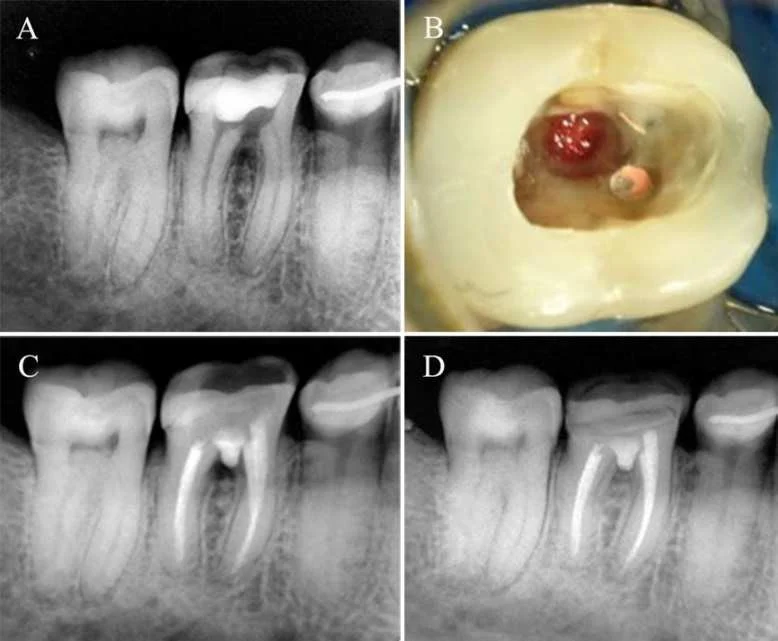

3. Chiến lược xử lý ngoại tiêu chóp

Đối với các trường hợp ngoại tiêu chóp, mục tiêu chính là thiết lập một “nút chặn” vững chắc.

- Kỹ thuật: Nên dùng Biodentine hoặc MTA để tạo rào cản chóp (khoảng 3-5mm).

4. Xử lý thủng chân răng với vật liệu nội nha hiện đại

Thủng chân răng là một trong những nguyên nhân hàng đầu gây thất bại nội nha nếu không được xử lý đúng cách.

- Quy trình: Kiểm soát viêm bằng Ca(OH)2 trước khi trám lấp lỗ thủng là chìa khóa thành công dài hạn.

- Lựa chọn vật liệu: * Sử dụng MTA nếu môi trường ống tủy khó cầm máu.